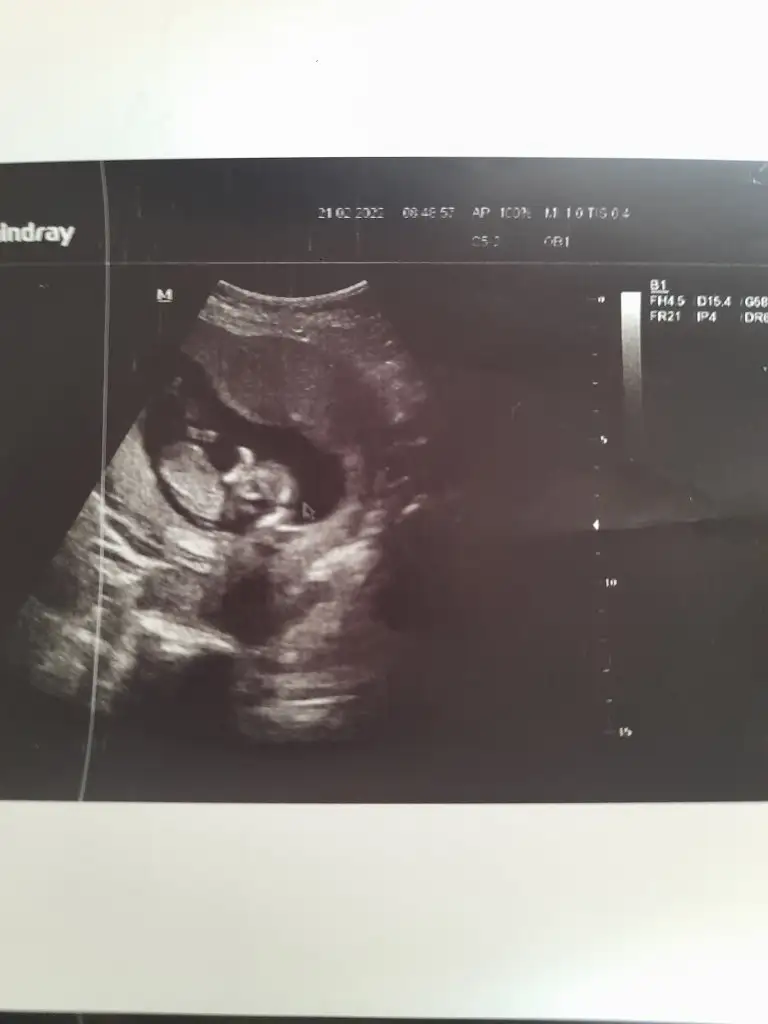

Merhaba 12+4 haftalık nub teorisi ile tahminde bulunabilir misiniz. Teşekkür ederim.

• 20220221_100239.webp

20220221_100239.webp

14,2 KB · Görüntüleme: 88